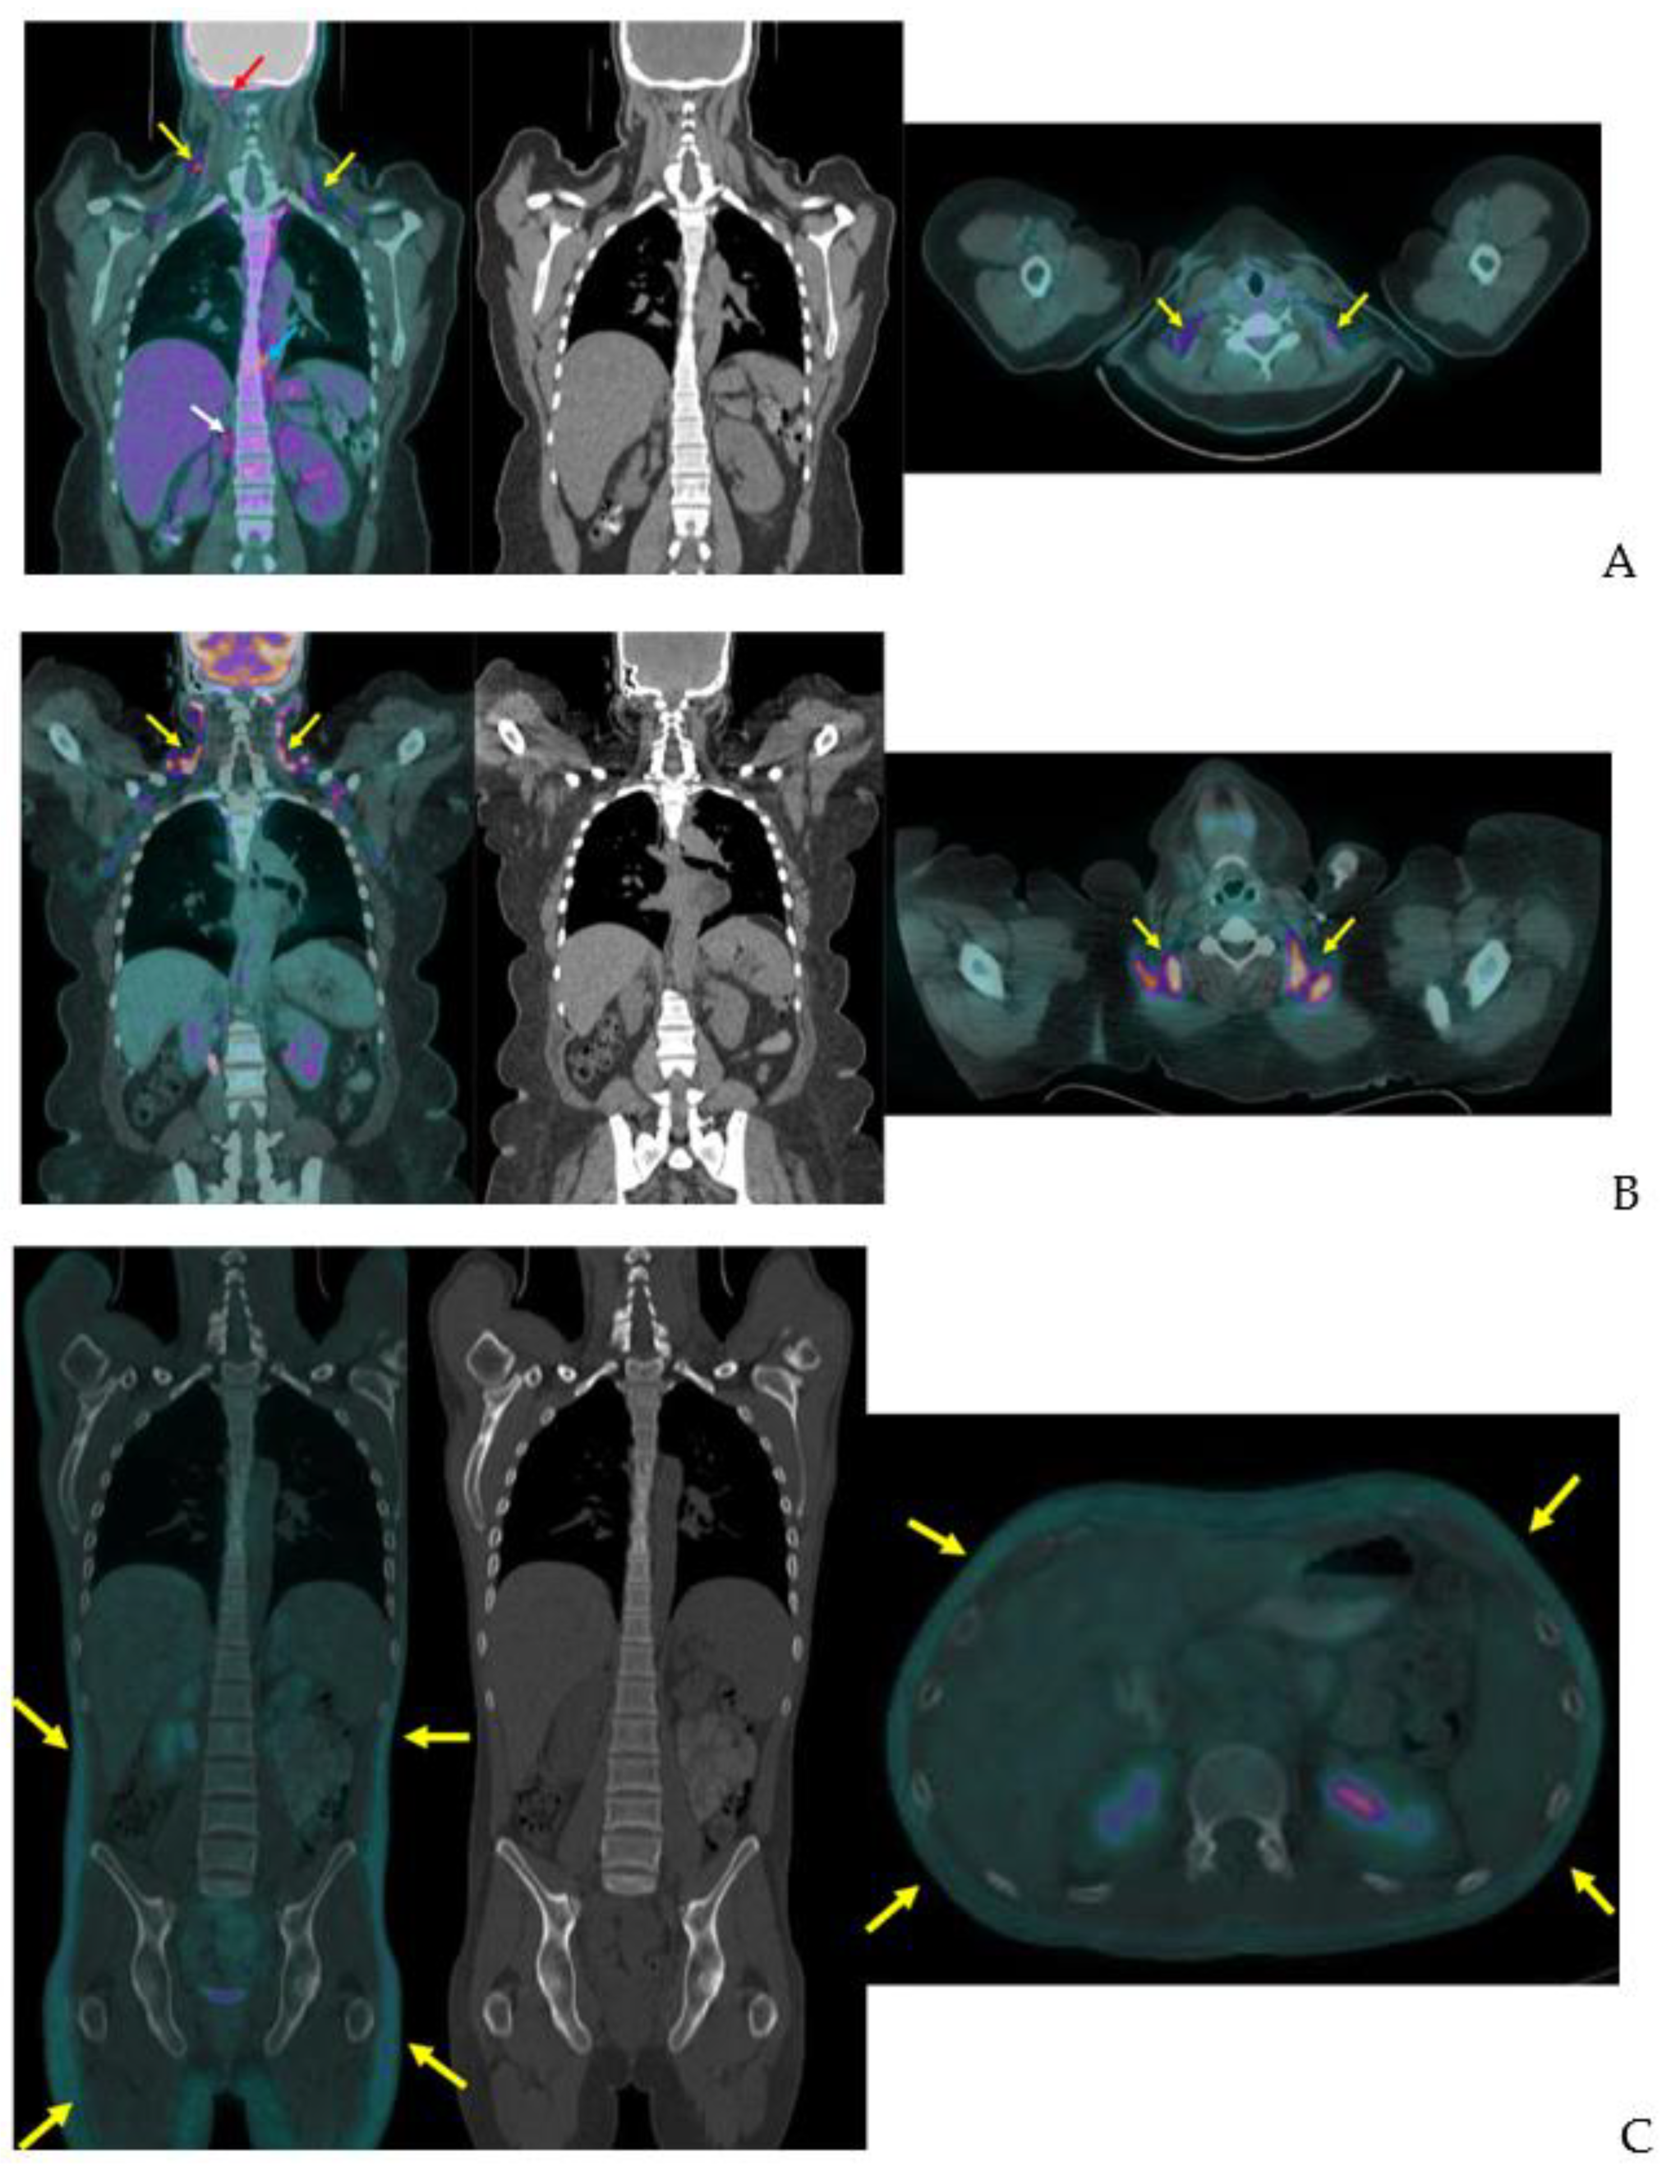

BAT is detected with other clinical and investigational radiotracers. 123I-metaiodobenzylguanidine (MIBG) SPECT/CT localizes sympathetic innervation by using a labeled norepinephrine analogue [75]. MIBG localizes BAT with similar sensitivity to FDG-PET/CT but is less temperature dependent [9,75,76]. The 11C PET tracer and norepinephrine analog 11C-meta-hydroxyephedrin has demonstrated sensitivity to BAT at thermoneutral conditions and its activity correlates with FDG uptake with acute cold in humans [77]. The commonly used SPECT/CT tracer 99mTc-methoxyisobutylisonitrile (MIBI), which localizes to tissues with high mitochondrial density, detects BAT in a non-temperature dependent manner as shown in an example from our clinical practice (Figure 9) [76,78]. 15O-labeled water PET/CT has been used in this setting to measure blood flow, which provides data to estimate tissue-specific metabolic rate using arterial oxygenation and known oxygen extraction fractions [77]. Din and colleagues combined 15O-labeled water PET/CT with inhaled 15O administration to directly measure tissue metabolic rate in humans [79]. The short (2 min) half-life of 15O allows for repeat PET scanning with another tracer on the same day [77,79]. Investigational radiotracer currently include the mitochondrial outer membrane translocator protein, visualized with 18F-FEPPA PET/CT and 11C-PBR28 PET/CT, the cannabinoid type 1 receptor, visualized with 18F-FMPEP-d2 PET/CT [80,81,82,83], and PD-L1, visualized with radiolabeled antibodies [84,85].

Figure 9.

99mTc-MIBI uptake in iBAT on a clinical scan. Supraclavicular BAT uptake shown coronal and axial fused 99mTc-MIBI-SPECT/CT (yellow arrows). Salivary gland uptake (white arrows) is normal.